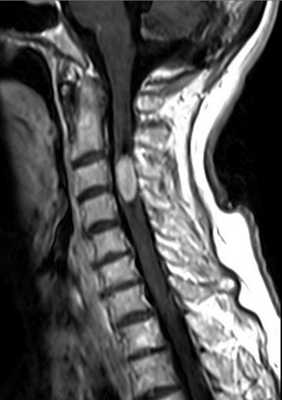

Миеломаляция, видимая при МРТ - это не конкретное заболевания, а изменения спинного мозга по типу локального отёка, последующего некроза, и заместительного глиоза. Миеломаляция при МРТ позвоночника может выявляться уже через 2 месяца после травмы. «Ранняя» (до 6 мес мосле травмы) миеломаляция может обратима. В большинстве случаев изменения сохраняются годами и сочетаются по данным МРТ с атрофией спинного мозга и сирингомиелитической кистой. Клинические проявления миеломаляции состоят из нижнего вялого парапареза, арефлексии и нарушений чувствительности ниже уровня поражения. Иногда встречается восходящее течение неврологического дефицита, что отражает диффузную миеломаляцию. Миеломаляция на МРТ выглядит как нечётко очерченный небольшой участок гиперинтенсивный на Т2-зависимых МРТ и гипоинтенсивный на Т1-зависимых МРТ.

МРТ шейного отдела спинного мозга. Миеломаляция. Т2-взвешенная сагиттальная МРТ.

Атрофией считается уменьшение передне-заднего измерения спинного мозга по результатам МРТ меньше 7 мм в шейном отделе и меньше 6 мм в грудном. Участок атрофии при МРТ может быть локальным или протяжённым, если он распространяется более чем на 2 позвонковых сегмента. Граница атрофии на Т2-взвешенных МРТ нечёткая. Распространённая атрофия является типичным отдалённым последствием спинальной травмы.

МРТ шейного отдела позвоночника. Компрессия и атрофия спинного мозга. Т2-взвешенная сагиттальная МРТ.